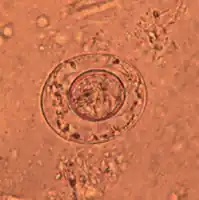

As its name implies (Ancient Greek: νᾶνος, nānos – dwarf), it is a small species, seldom exceeding 40 mm long and 1 mm wide. The scolex bears a retractable rostellum armed with a single circle of 20 to 30 hooks. The scolex also has four suckers, or a tetrad. The neck is long and slender, and the segments are wider than long. Genital pores are unilateral, and each mature segment contains three testes. After apolysis, gravid segments disintegrate, releasing eggs, which measure 30 to 47 μm in diameter. The oncosphere is covered with a thin, hyaline, outer membrane and an inner, thick membrane with polar thickenings that bear several filaments. The heavy embryophores that give taeniid eggs their characteristic striated appearance are lacking in this and the other families of tapeworms infecting humans. The rostellum remains invaginated in the apex of the organ. Rostellar hooklets are shaped like tuning forks. The neck is long and slender, the region of growth. The strobila starts with short, narrow proglottids, followed with mature ones.